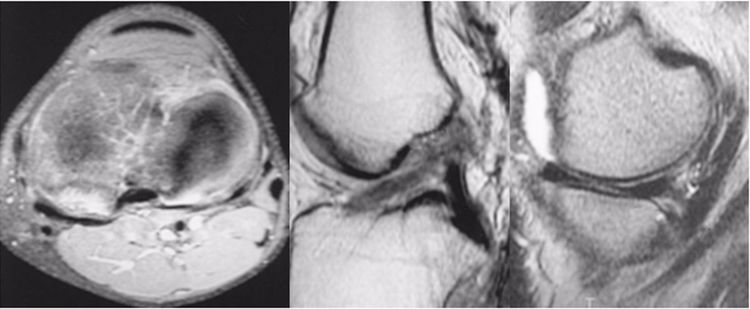

ACL损伤的间接征象:指ACL断裂后胫骨前移位出现的一系列改变。间接征象只能考虑可能有ACL损伤。

1.骨挫伤(轴移征):一旦ACL撕裂,胫骨就相对于股骨前移,使股骨外侧髁和胫骨外后方撞击,双方均出现水肿,而且膝关节屈曲的程度决定股骨髁挫伤的部位。

2.沟槽征:当股骨外髁骨因撞击造成的凹陷深度>2mm时称为沟槽征,代表受到撞击的暴力更大。

3.接吻征:膝关节过伸受伤时,胫骨前部撞击股骨髁前部,形成对称性骨挫伤;如果同时有一外翻力的话,膝关节外侧可出现对称性挫伤,这种对称性骨挫伤称为接吻征。也有人把轴移造成的股骨外侧髁和胫骨外后方水肿称为接吻征。

4.Segond骨折:胫骨平台前外侧撕脱骨折(胫骨平台腓骨尖上方,关节线下方的撕脱骨折),多因为下肢过度内翻加内旋暴力所致。骨折本身无特殊治疗。但其强烈提示ACL损伤(75–100%)。

5.前抽屉征:胫骨前移,外侧半月板后角裸露,由于MRI检查时病人为平卧位,胫骨应该因重力而后沉,因此前抽屉征往往暗示膝关节处于交锁状态。

6.ACL出现高信号:ACL信号紊乱,中央夹杂有较多高信号。不一定就是ACL损伤,需要与粘液性变、痛风结晶沉积等鉴别。

7.急性血关节:如果为急性ACL损伤,必然存在着大量的关节内积液(血),否则就不是。